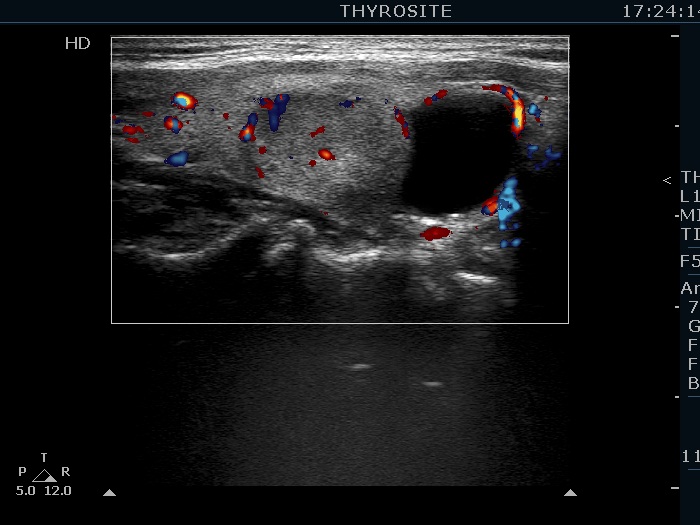

Ultrasonography. The thyroid was echonormal. There were several hypoechogenic lesions in the right lobe. The left lobe had an upper, solid and a lower cystic nodule. The former had both echonormal and moderately hypoechogenic parts and presented halo sign. The cystic nodule had a very tiny solid area in the dorsal part. Nonetheless, before aspiration it was unclear whether this would be a pure cyst or not. After aspirating 2 mL serous fluid a large, moderately hypoechogenic solid area replaced the previous cystic field and it became evident that this is in fact a central type cystic nodule.